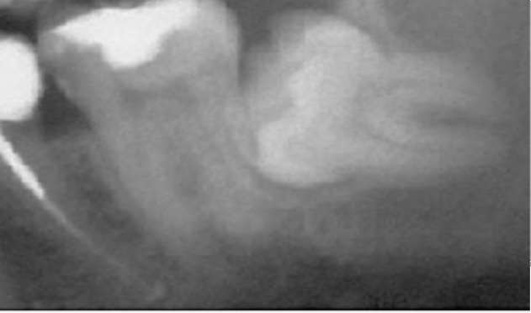

Этиология и патогенез. Важную роль в развитии пародонтита играют усиление повреждающего действия микробных скоплений десенной бороздки по мере как простого увеличения количества микробных масс, так и увеличения в их составе наиболее патогенных форм. Однако для реализации их разрушающего потенциала недостаточно только перечисленных изменений микробного состава. Необходимы снижение резистентности организма, неблагоприятное воздействие на пародонт нервно-соматических заболеваний, нарушения обмена и т.д. (рис. 14-20).

image

Рис. 14-20. Современная концептуальная модель пародонтита (Kornman K.S., 2008): ПМЯЛ - полиморфно-ядерные лейкоциты; ЛПС - липополисахариды; ММП - матриксные металлопротеиназы